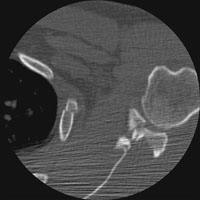

DGlenoid Fracture |

Glenoid fractures are usually the result of blunt trauma to the upper extremity. Subtle fractures can be difficult to detect on conventional radiographs; CT may be required for full diagnosis. A special glenoid fracture is termed the Bankart fracture. This consists of fracture of the inferior lip of the glenoid during anterior shoulder dislocation.